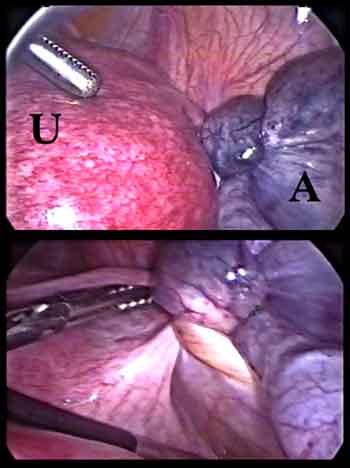

Ooforectomía laparoscópica presentando las tijeras HARMONIC ACE®+7 con hemostasia avanzada

Total Laparoscopic Hysterectomy featuring HARMONIC ACE®+7 Shears by Dr. Kondrup

Tijeras quirúrgicas HARMONIC ACE®+7

Hemostasia en laparoscopía

Ooforectomía laparoscópica presentando las tijeras HARMONIC ACE®+7 con hemostasia avanzada

Hemostasia en laparoscopía

Hemostasia en laparoscopía

Hemostasia en laparoscopía